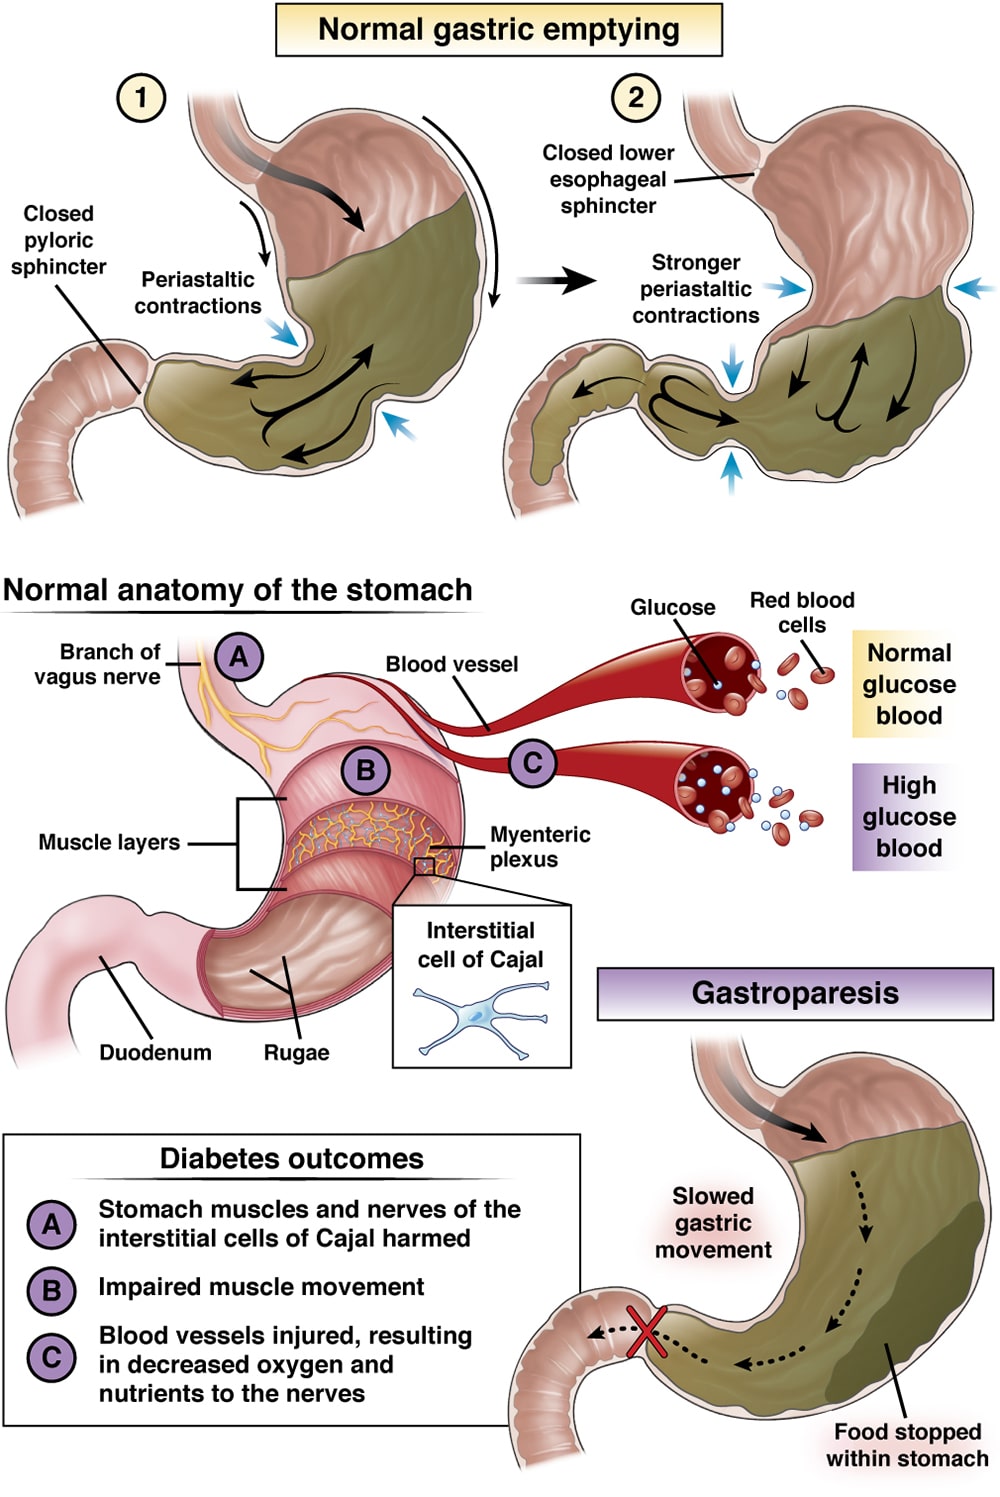

Diabetic Gastroparesis AGA GI Patient Center

Diabetic Gastroparesis AGA GI Patient Center